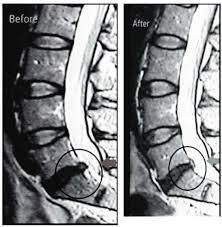

Spinal decompression is a non-surgical therapy designed to relieve pressure on the spine. The process involves gently stretching the spine using a specialized table, which creates negative pressure within the discs. This negative pressure helps retract herniated or bulging discs, allowing for increased blood flow and nutrient exchange, promoting healing.

The treatment gently stretches the spine, creating negative pressure within the discs. This allows bulging or herniated discs to retract and promotes the flow of healing nutrients.